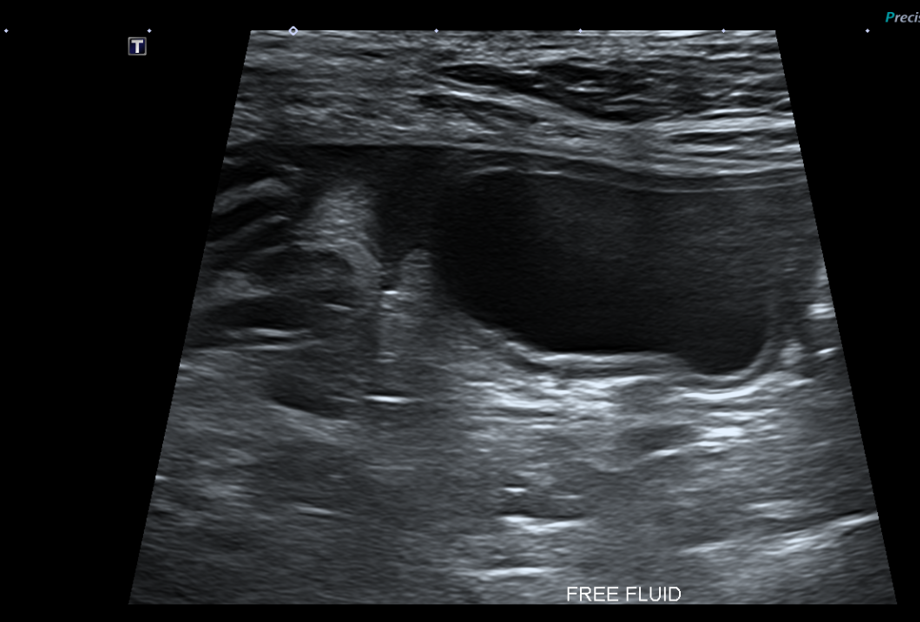

복부초음파

또한 복부 초음파상에서 뚜렷한 췌장 비후, 저에코성 음영, 주변 복막의 고에코성 소견 -> 확인되어 췌장염이 강력 의심되는 상황이었습니다.

Figure 2. 췌장 비후와 주변 복수 확인됨.

환자의 경우 뚜렷한 소화기 증상, 뚜렷한 염증 소견과 QPL 수치 상승, 복부초음파상 췌장염 비후, 복수 소견 확인되어 췌장염으로 진단되었습니다.